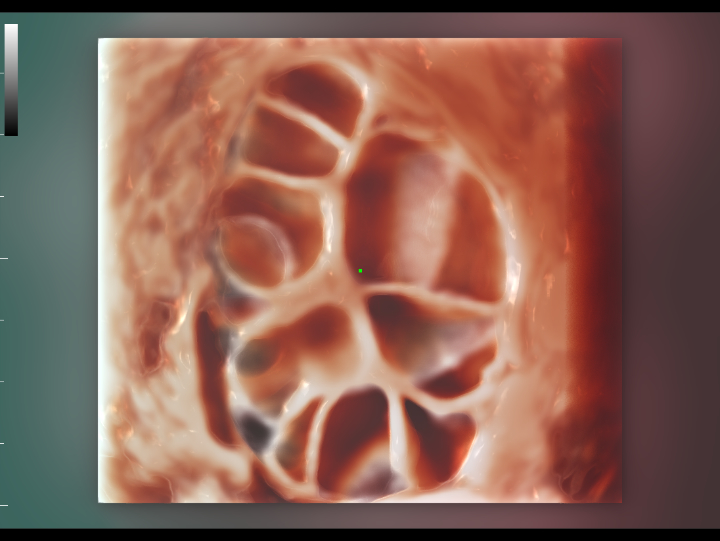

Pelvic ultrasound is considered as the first choice of imaging examination method to evaluate suspected gynecological diseases in women of all ages. Ultrasonography is usually the only necessary imaging examination to diagnose uterine, ovarian and adnexal diseases because of its wide availability, low cost and advantages of no ionizing radiation. With the development of volume ultrasound technology, 3D ultrasound has become a routine gynecological examination item. Through the acquisition of volume data, 3D ultrasound can display the uterus, cervix, ovary and uterine adnexa on any plane, and has more advantages in evaluating the uterine cavity.

UWN+ CEUS provides excellence contrast agent sensitivity and image penetration to get more diagnosis information for gynecology tumor or other difficult diseases. Also MindrayŌĆÖs STE (Sound Trouch Elastogtaphy) can quantitatively evaluate tissue stiffness which is helpful for previse diagnosis of difficult uterus, cervix and ovary diseases.